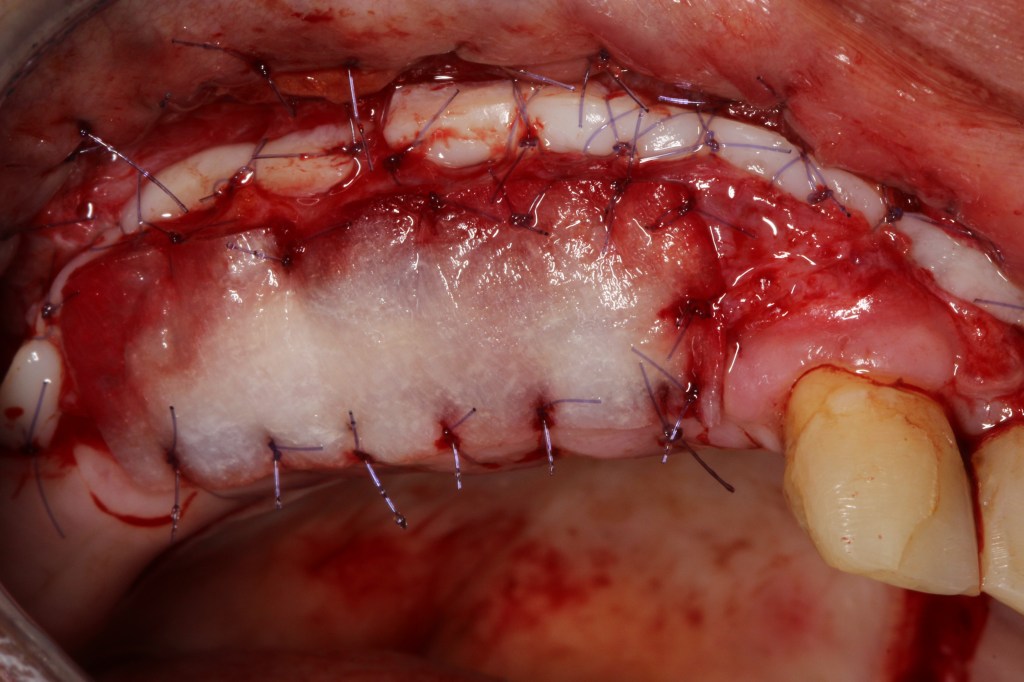

Reposition of the vestibule. FGG.Modified apically positioned flap (MAPF).

Modified apically positioned flap (MAPF). FGG.

Anterior maxilla reconstruction.

Implant placement after ridge augmentation.